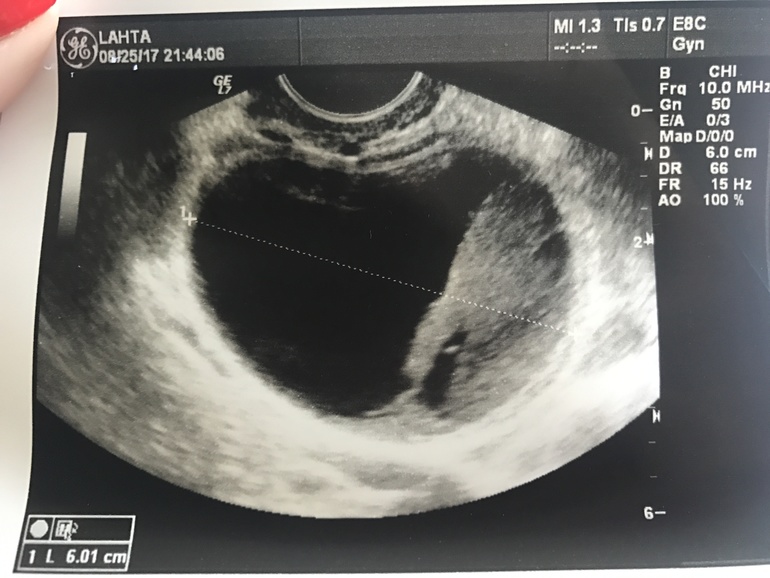

На 27 ДЦ (8 дпо) - вчера ужасно испортилось настроение и случилась истерика - во время неё - боли внизу живота , поехала делать УЗИ ... диагноз - многокамерная киста в левом яичнике (функциональная под вопросом). Причём большая 60 на 46 мм.. содержимое - жидкость. Свободная жидкость определяется, в скудном количестве.

Эндометрий 9мм.